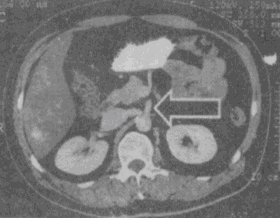

箭头所指的解剖结构是

A、肠系膜上动脉

B、肠系膜上静脉

C、脾静脉

D、脾动脉

E、门静脉

正确答案:

A